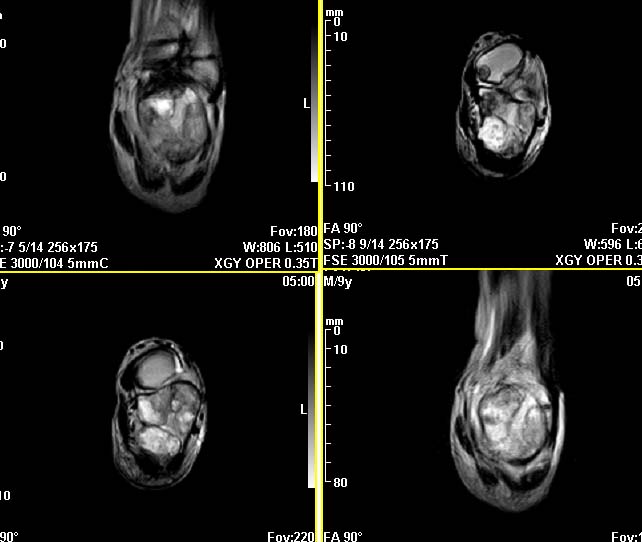

m,9y,左足肿痛半年,无皮肤发红,诱因为外伤后起因。无发烧,无其他疾病。临床考虑多发血管瘤。mri增强后有强化,请分析。是骨髓瘤吗?

左足多发囊状膨胀性骨质破坏,边较清,关节间隙及软组织未见明显异常。结合临床。可排除炎症性病变。病变中心为骨髓腔。有强化。中心坏死。嗜酸性肉芽肿可能大。

多发内生性软骨瘤

结合临床考虑血管瘤侵犯左足骨质。

今天从天津肿瘤医院传来消息:病理结果是非骨化性纤维瘤。